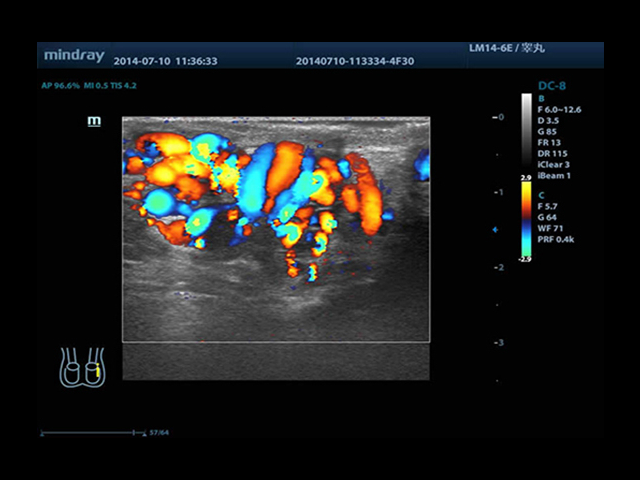

Mindray DC-8 Exp оснащен новым поколением датчиков с увеличенным количеством элементов и инновационной технологией "3T". Это позволяет достичь высокой детализации и качества изображения. Благодаря новейшей технологии iFlow, можно визуализировать даже самые мелкие сосуды и кровеносные пути.

• HR-flow™ - режим отображения кровотока с высоким временным и пространственным разрешением для точной и однородной визуализации сосудов, в том числе самых мелких

• Высокочастотный линейный датчик 38 мм Mindray l14-6NE